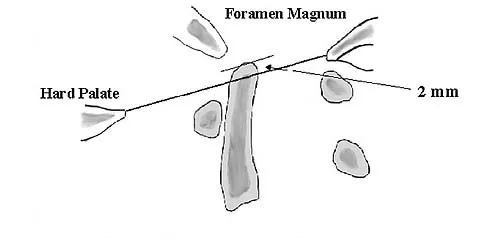

Question 72High Yield

The illustration shown in Figure 19 shows a Chamberlain line. What is the most likely diagnosis?

Explanation